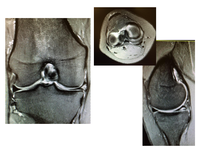

Magnetic Resonance Imaging ‘MRI’ is the most versatile imaging technique used in modern medicine. MRI does not use X-rays or ionising radiation, so it is much safer to use than CT or X-rays. It is also able to produce high-resolution images of all tissue types - bone, muscle, tendon, ligament, cartilage etc, meaning it is very useful in sports medicine.

Recently MRI machines with stronger magnets have been developed - 3 Tesla ‘3T’ MRI is able to produce the highest resolution images, and is particularly useful for ‘Cartilage mapping’, in patients with subtle cartilage injuries.